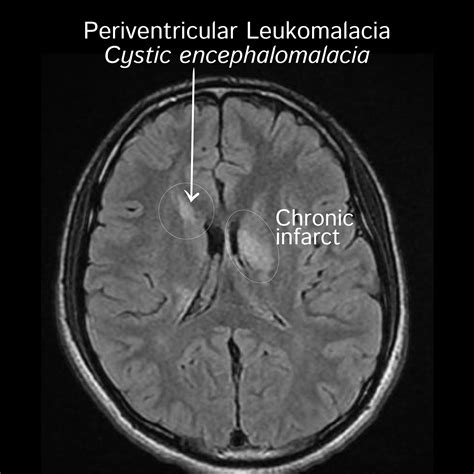

Periventricular White Matter Disease occurs when the integrity of this myelin or the underlying axons is compromised in the area surrounding the brain's ventricles—the fluid-filled cavities within the brain. This is often categorized under the broader umbrella of small vessel disease. When blood flow to these deep, sensitive areas of the brain is reduced, often due to stiffening or narrowing of the small arteries, the tissue begins to show signs of damage. Radiologists often describe these areas as "hyperintensities" or "lesions" on an MRI scan.